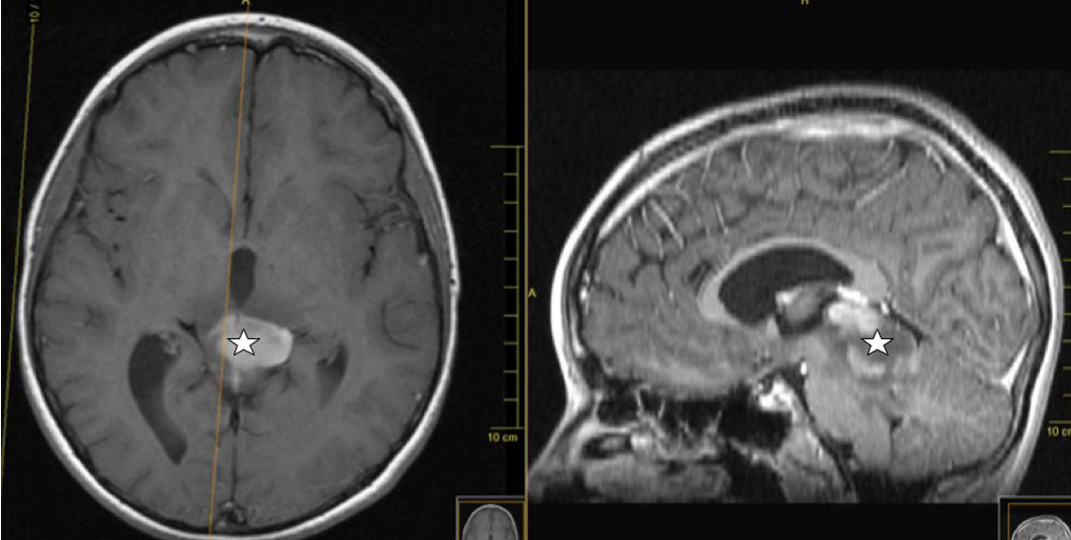

该论文还报告了一名11岁男孩因阻塞性脑积水出现头痛和复视。脑部核磁共振显示,在从小脑到松果体的四边形板上有一个轴向部分增强的病灶,引起脑积水。对病变进行次全切除,诊断为间变性神经节胶质瘤,并由参考中心确认。在较近的随访(3个月),男孩没有任何神经系统症状,并计划进行放疗和化疗。